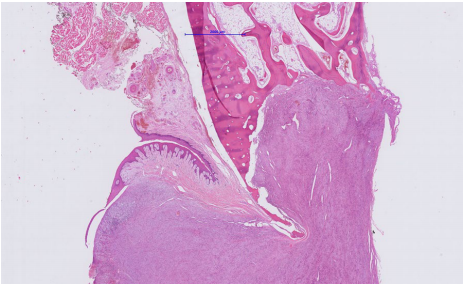

因此,病理学家建议切除肿瘤,并进行随后的组织病理学评估。治疗包括下颌骨的节段整体切除,包括第二前磨牙、第一磨牙和第二磨牙。骨切除术的水平边界位于下颌管正上方。保留了下牙槽神经。在肿瘤切除过程中,使用3D网格板来稳定剩余的下颌骨,以防止骨折。切除肿瘤的组织病理学检查显示,大量非典型梭形细胞呈未包膜、边界清楚的肿块。有丝分裂率为5/10。考虑到表面溃疡、下层致密骨的浸润和破坏以及所描述的形态,证实了LGMS的诊断(图4)。切除边缘清晰。

图4. 显微照片(苏木精和伊红染色,放大1.4倍)低倍镜下可见下颌骨广泛浸润并骨质破坏。